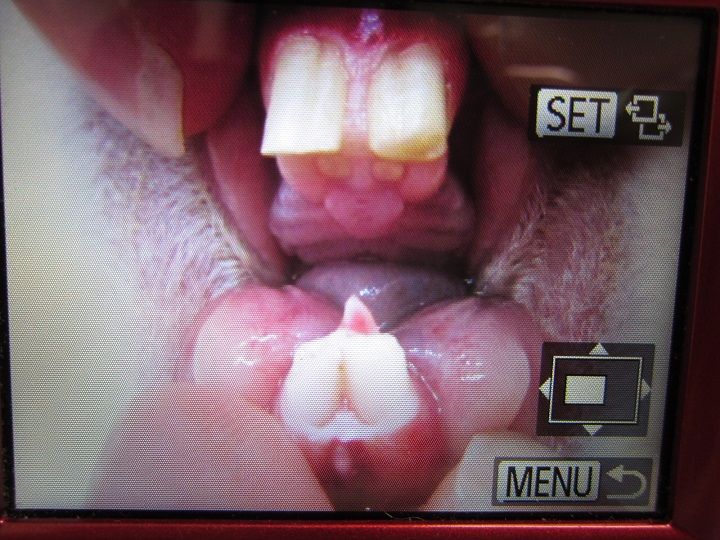

そして切歯は3週間あきました。

kagu0814

まずまずの伸びです。

kagu0815

かぐらちゃんの場合、まったくズレてしまってるパタンではありません。

うまくいきそうで、いかなさそうで…という現状です。

切歯に関しては、約3週間スパンでカットの処置を続けていく予定です。

処置後

kagu0816

歯の裏の歯茎は歯に接着してるわけではないので

そこを除けて傷つけないようカットしてもらいます。

合言葉は「ピヨっ」 (。 ^ 。)コケっ!

…上の切歯内側は無いことはない感じな話しかしてないので、

次回、も少し詳しく聞いてきます(。--)ノ …伸びてきてないような…

前回、様子を見た左側臼歯(奥歯)は、伸びて口内を傷つけてるわけでもなく、

今回も様子見です。まだぐらつき等ありませんが、左側は全体的に色も悪く

いずれ、抜けていくんではないか、との予想です。